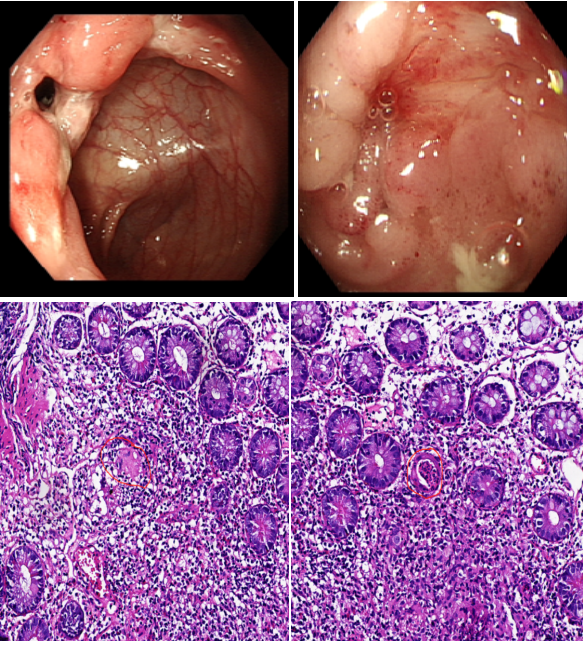

消化內(nèi)科二區(qū)通訊員譚思、李霞報道:近日,一位骨瘦如柴24歲小伙慕名來到衡陽市中心醫(yī)院消化內(nèi)科二區(qū)就診。該患者因腹瀉1年余,且伴有排便后肛周疼痛不適,輾轉多家醫(yī)院治療果,整個人變得郁郁寡歡接診時,患者體重僅有42KG,BMI只有14肛周有一1厘米左右的,有觸痛。何小梅醫(yī)生立即給予安排小腸CTE及腸鏡等檢查,發(fā)現(xiàn)腸道有節(jié)段性的潰瘍病變。病區(qū)主任舒寶蓮綜合臨床表現(xiàn)、生化指標、小腸CTE、腸鏡及病理結果診斷患者“克羅恩病肛周病變”在對患者疾病的活動程度進行評估,基于患者年齡以及伴有肛周膿腫2項高危因素綜合考慮,給與患者使用生物制劑“英夫利西單抗”對癥治療。目前患者腹瀉及肛周疼痛有明顯的好轉,患者及母親對診療效果非常滿意。出院時,患者充滿感謝地對醫(yī)務人員說:“醫(yī)生很快就找到了病因,又通過個體化的營養(yǎng)治療增加了我的體重,醫(yī)務人員還耐心地對我進行健康宣教與心理疏導,謝謝你們解決了困擾我生活的大問題

克羅恩病(CD):是一種病因尚不明確的胃腸道慢性炎性肉芽腫性疾病。病變多見于末端回腸和臨近結腸,但從口腔至肛門各段消化道均可受累,呈節(jié)段性或跳躍式分布。臨床上以腹痛、腹瀉、體重下降腹塊、瘺管形成、肛周病變及腸梗阻為特點,可伴有發(fā)熱的全身表現(xiàn)以及關節(jié)、皮膚、眼、口腔粘膜等腸外損害。發(fā)病年齡多在15-30歲,但首次發(fā)作可出現(xiàn)在任何年齡組。本病有終生復發(fā)傾向,重癥或者遷延不愈。預后不良??捎心c梗阻、腹腔膿腫、消化道出血及結癌變等并發(fā)癥發(fā)生。

克羅恩病的診斷需結合臨床表現(xiàn)、實驗室指標、影像學(小腸CTE)、腸鏡及病理。